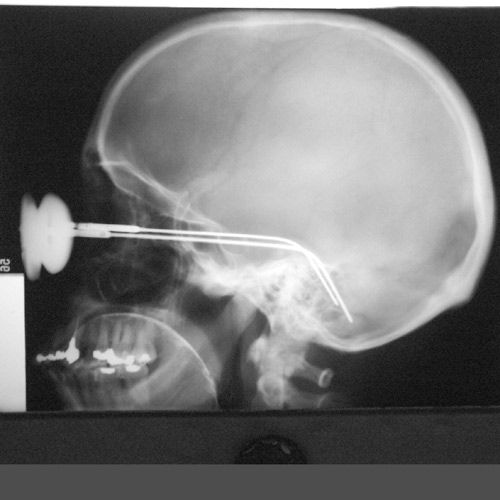

Под рентгеном